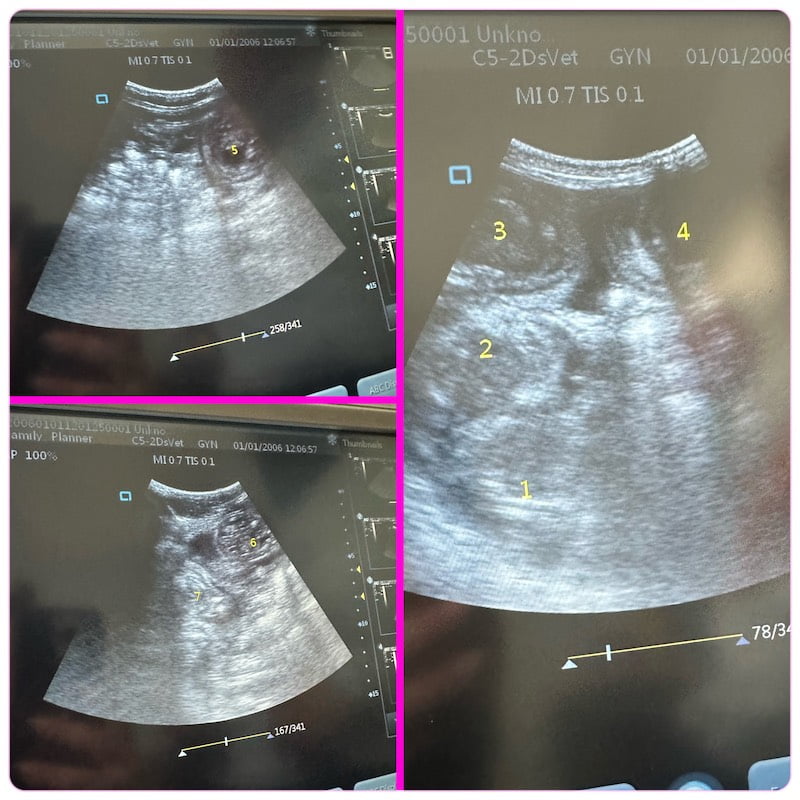

Narla: ultrasound of upcoming litter due around 23rd April